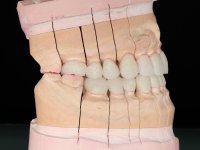

Paciente do sexo masculino, com 42 anos de idade, não fumador. Apresentava uma reabilitação metalo -cerâmica feita há mais de 10 anos com exposições radiculares e infiltrações. No maxilar superior apresentava uma coroa no 1.1,uma ponte de dois elementos no 2.1 e 2.2.e uma ponte de 4 elementos nos dentes 2.4,2.5,2.6 e 2.7 com o 2.6 como pôntico. Os dentes 1.6/1.5/1.4/1.3/1.2/1.1/2.1/2.2/2.3/2.4/2.5 e 2.7 apresentam tratamento endodôntico radical com o 2.4/2.5 e 2.7 a necessitarem de ser refeitos. No maxilar inferior apresentava uma ponte metalo-cerâmica de 4 elementos nos 4 incisivos e uma ponte de 3 elementos (3.3 e 3.4) com um dente supranumerário como pôntico. Os dentes 4.6/4.5 e 4.2 apresentavam tratamento endodôntico com o 4.2 a necessitar de ser refeito. Os dentes 4.3 e 4.4 apresentavam extensas cáries linguais com algum comprometimento mesial. As peças protéticas apresentavam-se infiltradas com exposição radicular associada. Apresentava uma D.V.O. diminuída e uma mordida cruzada lado direito. O paciente tinha uma satisfatória saúde periodontal e uma boa higiene oral.

Foi proposto ao paciente fazer uma reabilitação total com infraestruturas em zircónia revestidas a cerâmica. No maxilar superior, seriam realizadas 6 coroas (1.3/1.2/1.1/2.1/2.2/2.3), uma ponte de 3 elementos (1.4/1.5/1.6) e uma ponte de 4 elementos (2.4/2.5/2.6 e 2.7). No maxilar inferior, foram propostas 7 coroas (4.3/4.2/4.1/3.1/3.2/3.5 /3.6) e duas pontes (4.4//4.5/4.6) e (3.3/3.4#/3.4).O objetivo seria subir a D.V.O., descruzar a mordida do lado direito, eliminar as infiltrações e as exposições radiculares e reabilitar o paciente com estruturas protéticas com aspeto mais natural.